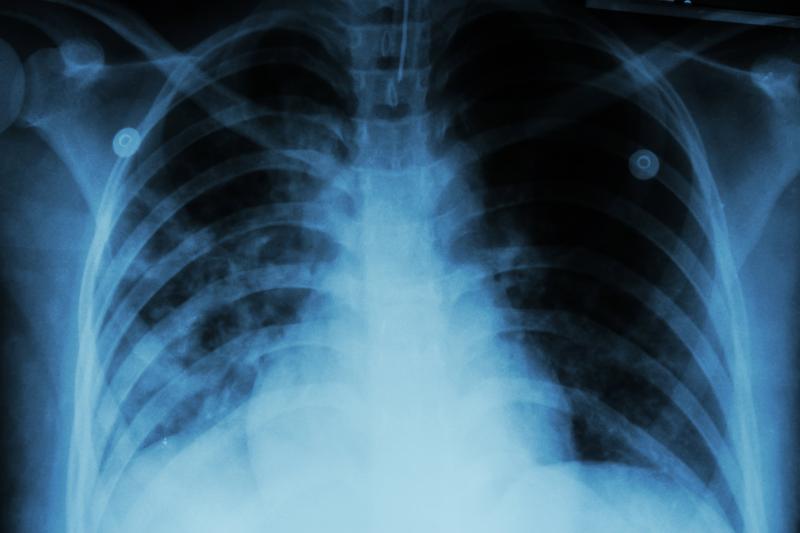

Increased body mass index (BMI) does not seem to raise the risk of developing sarcoidosis, according to a study. Furthermore, the presence of obstructive sleep apnoea (OSA) even confers protection.

A total of 10,512 sarcoidosis patients and 2,709,884 control patients were included in the analysis. There was no significant association seen between BMI and the rate of developing sarcoidosis. Post hoc statistical power calculations validated that this null result was meaningful and not due to insufficient statistical power.

Meanwhile, a diagnosis of OSA had a protective association with the odds of developing sarcoidosis. Multivariable conditional logistic regression model revealed a 49.0-percent lower likelihood of sarcoidosis in OSA patients in comparison with control patients. The estimate was adjusted for age, sex, and BMI in the same 12-month period.